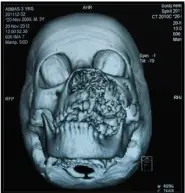

PATIENT THEN REPORTED TO OUR UNIT IN 2012. INCISIONAL BIOPSY REVEALED AMELOBLASTIC FIBROMA AND CBCT OF THE FACE WAS DONE WHICH GAVE AN IMPRESSION OF HEMANGIOMA / RHABDOMYOSARCOMA.

3D CT SCAN